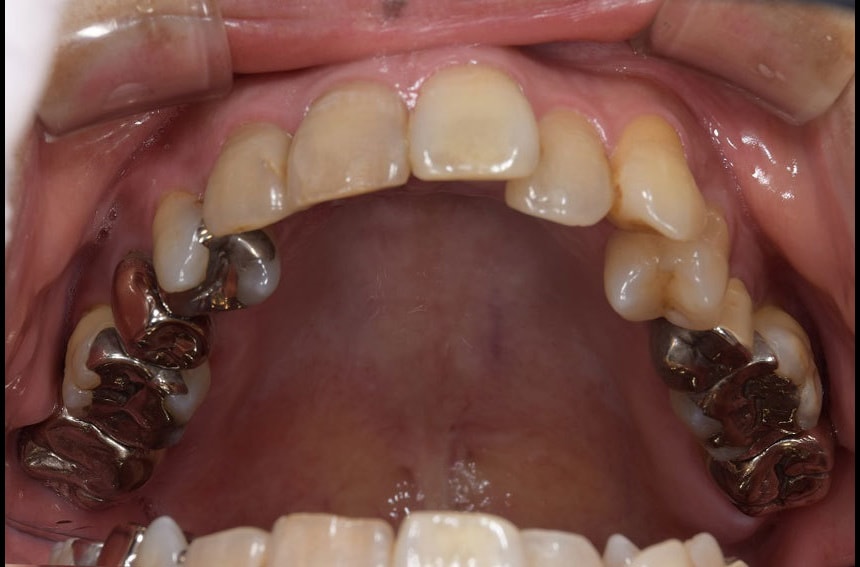

上の歯の治療前後

最小限の矯正治療や過去に治療した銀歯の隙間から虫歯になった歯や神経の再治療を行いました。もう少し修正が必要なのですが、部分矯正も含め長い治療になり、とりあえずはお疲れさまでした。